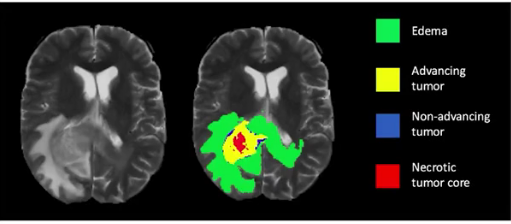

或许很多人心中都有一个疑问,那便是我们是否需要如此精心的预测一张图像中的目标?其实,对于绝大数CV应用场景来说,仅依赖目标检测是可以解决的。但是,这并不意味图像分割就没有存在的意义。举个简单的例子,比如癌症,大家都知道这个都是由癌细胞扩散所造成的。通常,癌细胞的形状在确定癌症的严重程度中起着至关重要的作用,这时候图像分割便派上用场了。